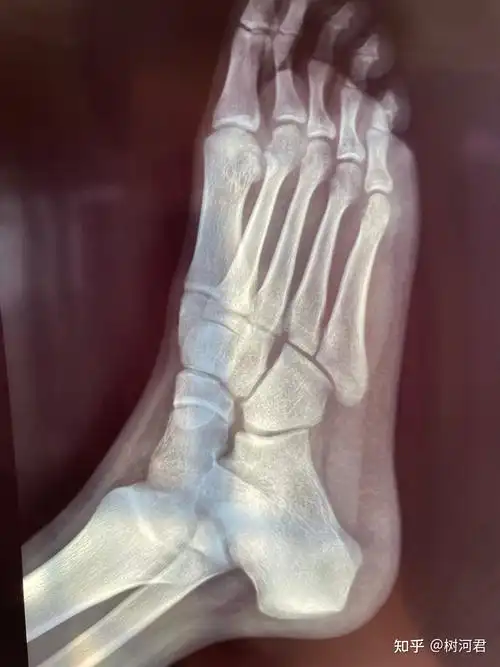

第五跖骨基底部裂纹骨折忧伤记录